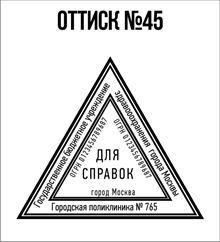

- Первое – это огромный выбор клише, то есть изображений будущей печати. Посмотрите, пожалуйста, чуть выше у нас на данной странице сайта имеется галерея изображений. Вы можете выбрать любое понравившееся Вам и сделать заказ;